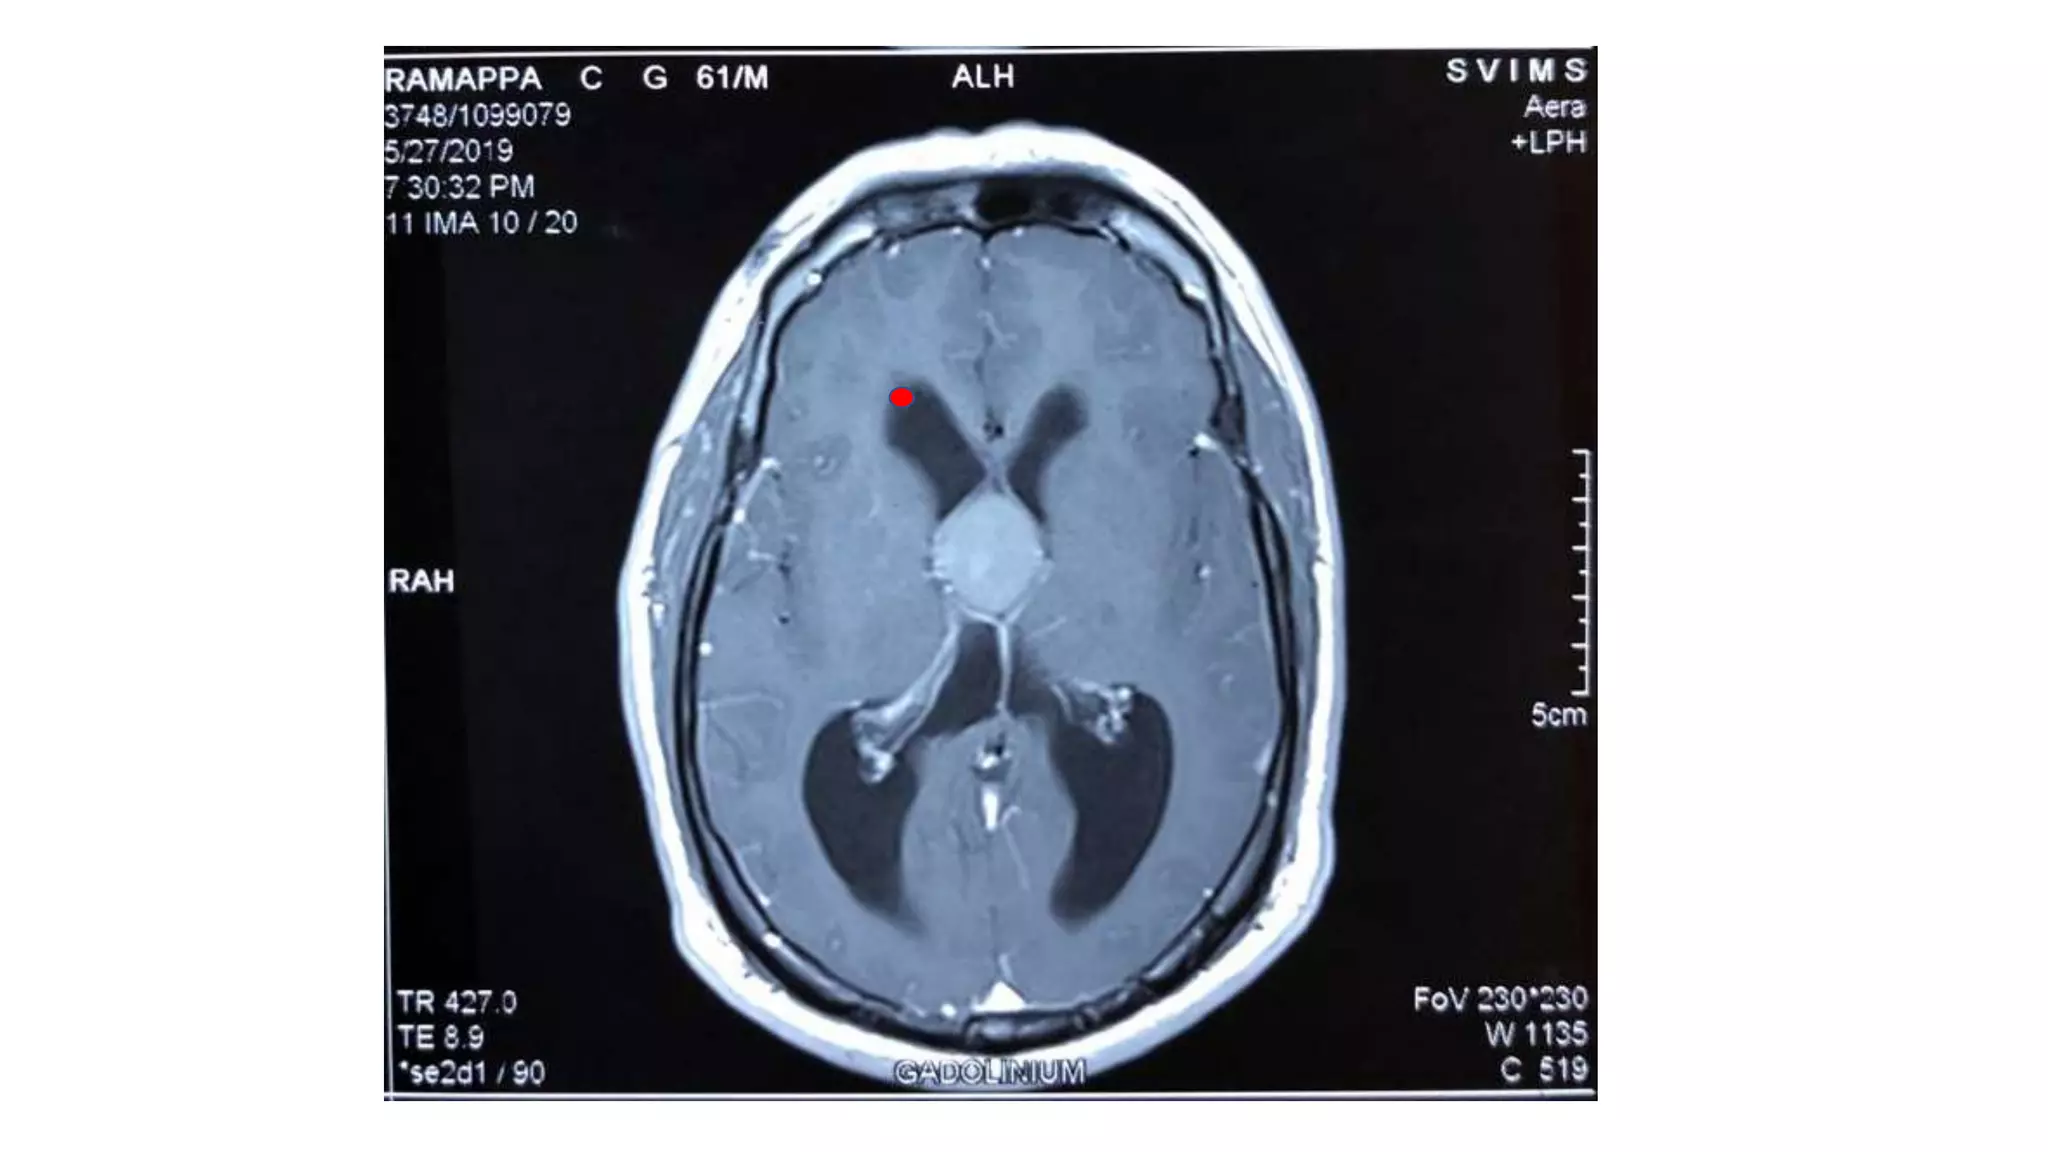

Trans callosal:

• No hydrocephalus and dilated ventricles.

• Entry point will be 1.5 lateral to midline to

avoid the superior saggital sinus

• Brain retracted superior callosal arteries

are retracted

• Entry will be between the Fornices and

then into any of the foramen of Monroe

• Enblock cyst excision is possible in trans

callosal approach.